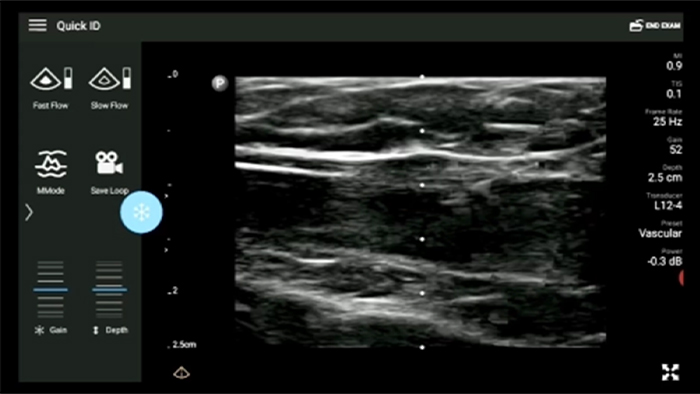

Disminuya las complicaciones de las inserciones de CVC

La guía por ultrasonido en tiempo real puede mejorar la precisión y la seguridad de las inserciones de CVC.

• Rango extendido de frecuencias de operación entre 12 y 4 MHz • Tamaño de apertura: 34 mm • 2D, Doppler orientable a color, Modalidad M, XRES avanzado e imágenes armónicas multivariables, SonoCT • Imágenes de alta resolución para aplicaciones superficiales: tejidos blandos, vasculares, superficiales, musculoesqueléticos y pulmonares • Marcador de línea central • Transductor USB-C con cable reemplazable